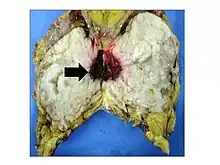

.jpg.webp)

Malignant phyllodes tumors can behave similarly to sarcomas leading to development of blood-borne metastases.[16] Approximately 10% of phyllodes tumor develop distant metastases and this occurrence is higher (20%) in patients with histological-identified malignant tumors.[16] The most common site for distant metastases include the lung, bone, and abdominal viscera.[17] In more insidious cases, the parotid region has also been described in literature.[18]